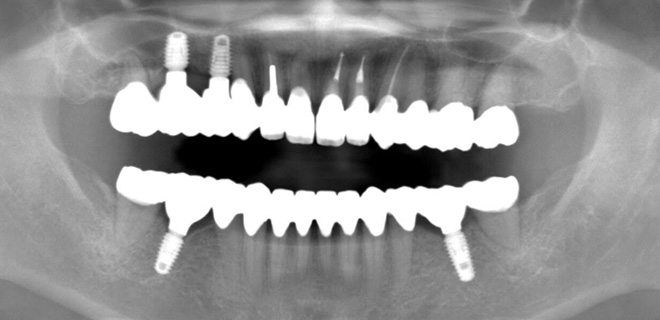

治療後のレントゲン写真

患者様は50代女性、治療期間は1年。

この症例の治療費

奥歯スタンダードインプラント4本→1,760,000円(税込)

《インプラント1本あたり440,000円(税込)》

セラミック20本→2,640,000円(税込)

《セラミック1本あたり132,000円(税込)》

咬合再構成(全ての仮歯と噛み合わせ治療)→792,000円(税込)

総額5,192,000円(税込)

この症例のリスク

治療中の仮歯が外れたり壊れたりすることがあります。

インプラントが稀に脱落することがあります。

セラミックが稀に欠けたり割れたりする可能性があります。